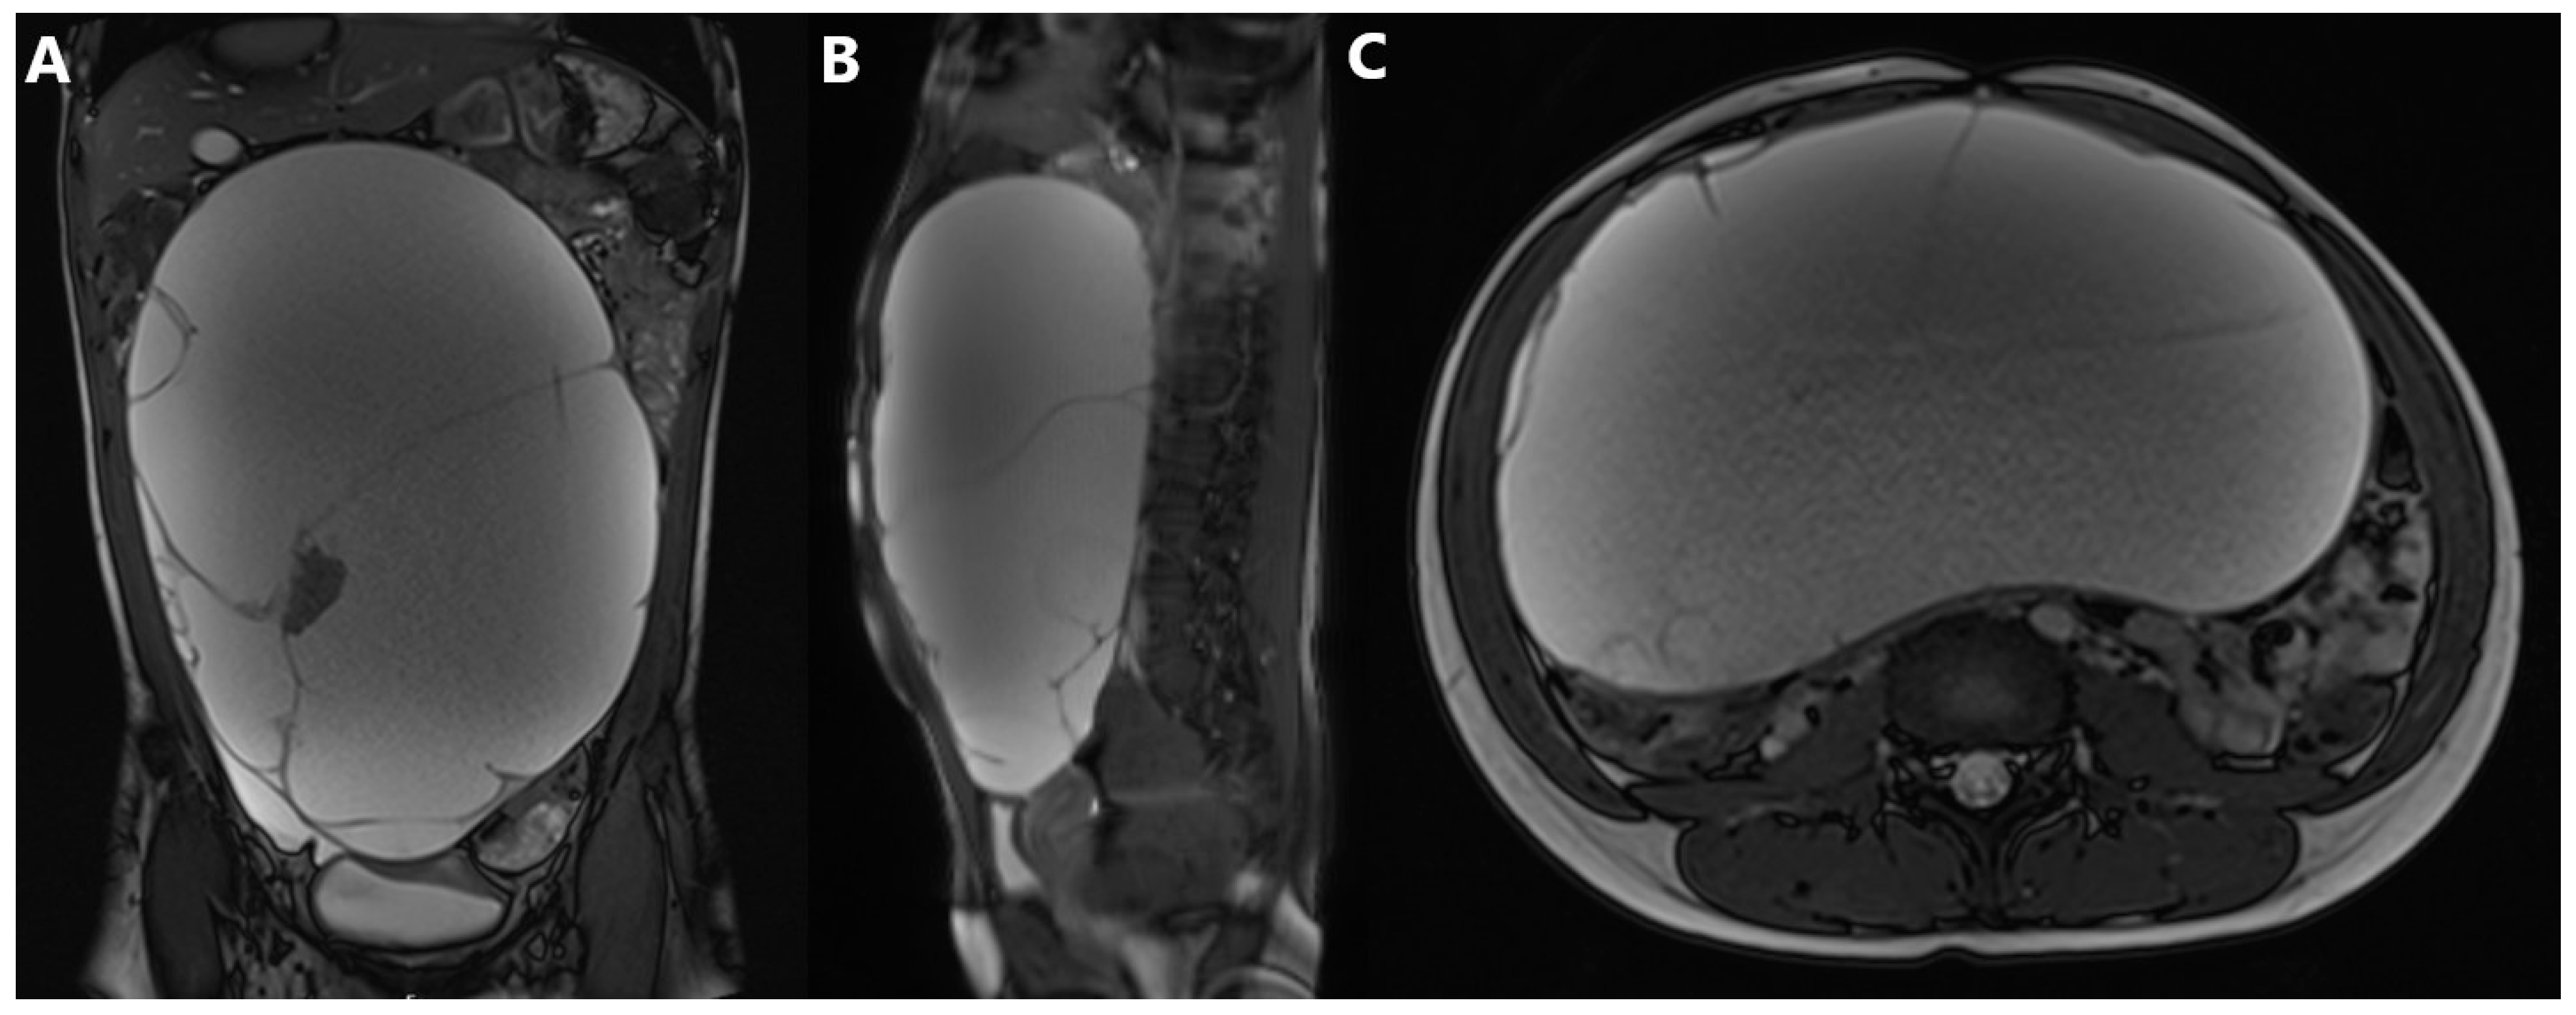

2.3. Diagnostic Assessment